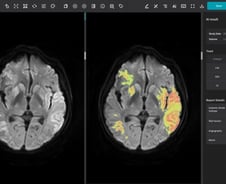

제이엘케이는 자사의 의료 인공지능(AI) 솔루션에 사상 첫 보험수가가 적용되면서 글로벌 시장에서 경쟁력이 한층 강화됐다고 7일 밝혔다. 제이엘케이의 뇌경색 유형 분류 솔루션인 'JBS-01K'는 지난달 건강보험정책심의위원회를 통과해 조만간 의료 현장에서 비급여로 비용 청구가 본격적으로 시작될 예정이다. 회사에 따르면 JBS-01K는 모든 뇌졸중 환자가 촬영해야 하는 확산강조영상(Diffusion Weighted Image, DWI)에 적용돼 유형 분석 결과를 제공한다. 뇌졸중 치료에 필수적인 분석 정보를 제공하는 만큼 임상적 중요도가 높아 의료 현장에서 많은 활용이 예상된다. 제이엘케이는 AI 의료기기의 첫 번째 비급여 적용을 통해 향후 안정적인 수익이 확보될 것으로 내다보고 있다. 특히, 보유 중인 다른 뇌졸중 제품 또한 순차적으로 비급여 시장 진출을 앞두고 있어 추가적인 매출 확대가 가능할 것으로 전망된다. 해외 진출에도 탄력이 붙을 전망이다. 제이엘케이는 이미 강력한 기술력을